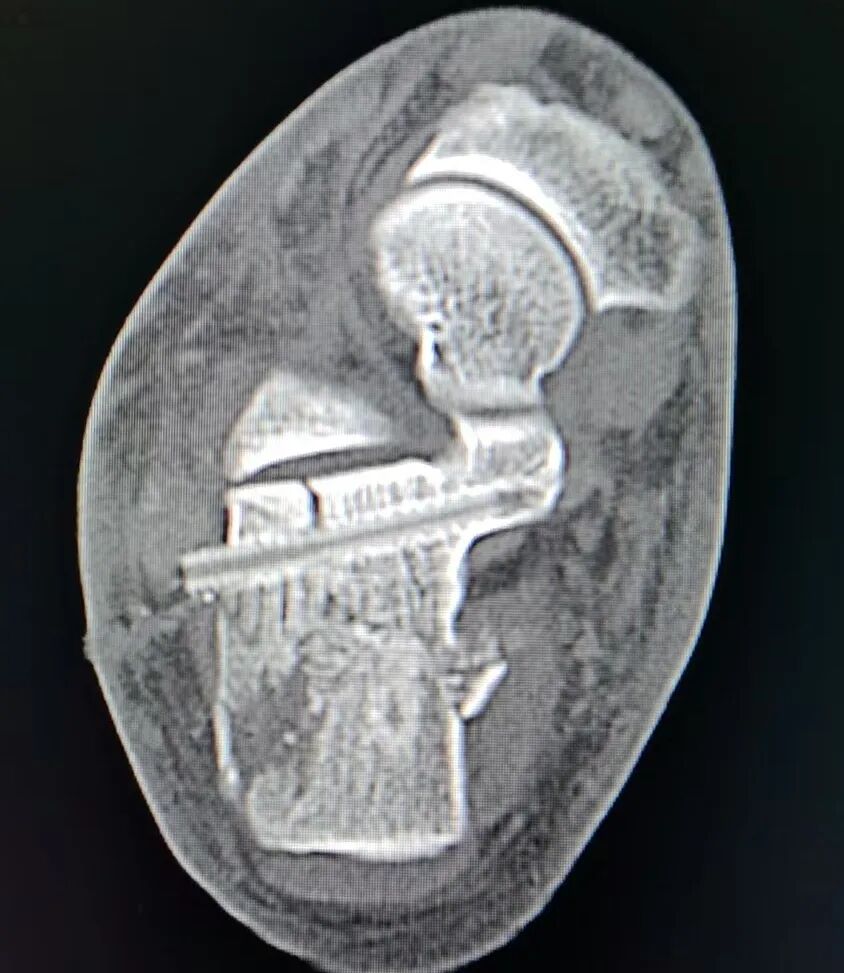

该男性患者因右足高出跌落伤1小时入院。入院时右足肿胀明显,宽度增加,触痛明显,CT显示骨折移位明显。以往常规治疗需要等肿胀消退之后,大约5-7天,才可以进行手术治疗。

经过术前讨论,结合患者病情,魏宪会医疗团队决定运用新技术,第二天即行手术治疗,术中采取先进的撬拨技术恢复骨折的正确对位对线,用可吸收螺钉固定,术后第二天肿胀即明显消退,肢体活动恢复正常。

术后复查影像